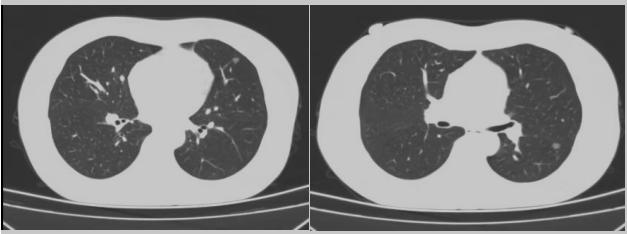

病例二:42歲的范女士,半年前體檢時發(fā)現(xiàn)雙側(cè)多發(fā)肺結(jié)節(jié),平時沒有什么不適。四個月后再次復(fù)查胸部CT,左上肺及下肺多發(fā)的磨玻璃結(jié)節(jié),其中下葉9mm的結(jié)節(jié)定為高危病灶??吹浇Y(jié)果范女士坐不住了,多方打聽慕名找到了市二院院長王瑾,經(jīng)“肺結(jié)節(jié)MDT”團隊會診后,決定手術(shù)治療。入院后,胸外科副主任醫(yī)師薛飛詳細(xì)與范女士溝通,并利用Mimics做好了術(shù)前肺部三維重建手術(shù)規(guī)劃,打消了范女士心中的顧慮。經(jīng)過前期充分準(zhǔn)備后,歷經(jīng)1小時30分,完成“胸腔鏡下左肺上葉舌段楔切及左肺下葉背段切除術(shù)”,術(shù)后病理檢查結(jié)果確診為左肺微浸潤性腺癌。在胸外科團隊的悉心照顧下,患者術(shù)后恢復(fù)良好,一周后順利出院。